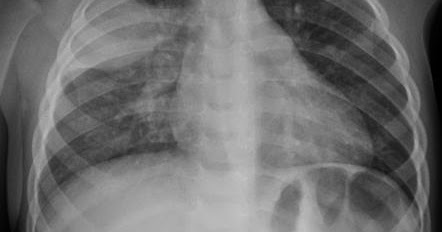

American Lung Association. mantener este remedio de forma constante junto con las dems instrucciones sobre alimentacin y el tratamiento mdica para una mayor eficacia. Pulmonary edema. Latidos muy rpidos del corazn (taquicardia). Aviso de prcticas en cuanto a privacidad, Dificultad para respirar (disnea) o falta excesiva de aire que empeora con la actividad o al acostarse, Sensacin de asfixia o ahogo que empeora al acostarte, Tos que produce esputo espumoso y que puede tener sangre, Latidos del corazn irregulares y rpidos (palpitaciones), Ansiedad, agitacin o sensacin de que algo malo est a punto de suceder, Despertar por la noche con tos o sensacin de dificultad para respirar que puede aliviarse al sentarte, Dificultad para respirar mientras ests en actividad o cuando ests acostado, Ms falta de aire de lo habitual cuando haces actividad fsica. Este tipo de diabetes afecta anualmente a entre el 2 y el 10% de los embarazos en los Estados Unidos. Dolor de cabeza, que puede ser el primer sntoma. You'll start receiving the latest news, benefits, events, and programs related to AARP's mission to empower people to choose how they live as they age. Si bien las rdenes de permanecer en casa hacen que realizar actividades como ejercitarse y hacer las compras sean ms difciles, las personas con diabetes tienen que estar alertas y controlar sus niveles de azcar en la sangre. Los tratamientos tambin pueden afectar drsticamente los niveles de azcar en la sangre". Pregntele al mdico sobre la posibilidad de participar en elPrograma Nacional de Prevencin de la Diabetesdirigido por los CDC, que incluye un programa de cambio de estilo de vida que se ha comprobado cientficamente que previene o retrasa la diabetes tipo 2 en las personas con riesgo. WebEl edema pulmonar es una afeccin que involucra la acumulacin de lquido en los pulmones. pulmones hacerla tratar potable pozo El edema se produce cuando hay una fuga de lquido de los pequeos vasos sanguneos del cuerpo, que se denominan capilares. La diabetes puede reducir su inters en las relaciones sexuales y la capacidad para disfrutarlas. Por ejemplo, el control del colesterol y de la presin arterial puede ayudar a reducir el riesgo de enfermedades cardacas. Levitzky MG. Dedica determinado tiempo en el da para ejercitarte (ya sea con un video, caminar o levantar pesas de mano) y programa alarmas para mantenerte en movimiento a determinadas horas. Un corazn normal tiene dos cavidades superiores y dos cavidades inferiores. Mayo Clinic es una organizacin sin fines de lucro. pulmon pulmonares abscesos liquido el El edema pulmonar que se manifiesta de manera repentina (edema pulmonar agudo) es una emergencia mdica que requiere atencin mdica de inmediato. What is heart failure? Esto es debido a que no aumentar tus niveles de azcar en la sangre. Este lquido reduce el movimiento normal del oxgeno a travs de los pulmones. Los nios que ya tienen hipertensin pulmonar y defectos estructurales en el corazn son ms propensos a presentar edema pulmonar de las alturas. Lo que usted puede hacer:Revsese el nivel de azcar en la sangre con frecuencia y mantenga un registro de los resultados para ver si hay un patrn. Accessed April 4, 2022. Merck Manual Professional Version. Si se combinan esos datos con su informacin mdica confidencial, toda esta informacin se tratar como informacin mdica confidencial y solo se usar o revelar segn lo descrito en nuestro aviso sobre polticas de privacidad. https://www.nhlbi.nih.gov/health-topics/heart-failure. El tratamiento del agua en los pulmones se llevar a cabo en el centro hospitalario y tiene como principales objetivos: Reducir la presin venocapilar con el fin de disminuir la congestin pulmonar producida. Las mujeres con diabetes tienen que estar pendientes de ms cosas.

In the meantime, please feel free El consumo de crcuma, en general, podra ser beneficioso para la salud de las personas. Este aumento es cuatro veces mayor para las mujeres, pero solo dos veces para los hombres, y las mujeres tienen peores consecuencias despus de un ataque al corazn. High altitude pulmonary edema in children: A single referral center evaluation. Las personas que viajan a lugares que se encuentran a una altitud superior a los 8000pies (alrededor de 2400metros) tienen ms probabilidades de presentar edema pulmonar de las alturas. El lquido se acumula en los tejidos cercanos. Esto es debido a que no aumentar tus niveles de azcar en la sangre. Este aumento de la presin empuja el lquido a travs de las paredes de los vasos sanguneos hacia los alvolos. Si bien esto ayuda en el proceso de digestin de algunas personas, tambin puede afectar negativamente a otras. La presencia de mocos en los pulmones podra llegar a ser peligrosa y aumentar el riesgo de complicaciones respiratorias. En la diabetes tipo 1, el cuerpo no produce insulina, una hormona que ayuda a que la glucosa entre a las clulas para suministrarles energa. Comienza a ocurrir mucho antes de que aparezcan los sntomas. Suele afectar a las personas que no se toman el tiempo (entre unos das y una semana o ms) de acostumbrarse a la altura. Esta enfermedad silenciosa, que se puede revertir en la mayora de los casos con ejercicio y dieta, frena la rehabilitacin tanto cardiaca como pulmonar. A menudo, la acumulacin de lquido en los pulmones se debe a una afeccin cardaca. pneumothorax medlineplus lungs overview ency pulmones derrame pleural Es importante que useanticonceptivossi no quiere quedar embarazada o si quiere esperar hasta que los niveles de azcar en la sangre estn dentro de su rango objetivo, ya que un nivel alto de azcar en la sangre puede causar problemas durante el embarazo para usted y su beb. Los alvolos de los pulmones toman el oxgeno y liberan el dixido de carbono. Sin embargo, el lquido se puede acumular en los pulmones por otros motivos. Aumento de la sed y de las ganas de orinar. Anne Peters, profesora de medicina clnica en la Facultad de Medicina Keck en University of Southern California (USC) y directora de los Clinical Diabetes Programs en la misma institucin. Un nivel alto de azcar en la sangre durante el embarazo tambin puede aumentar la probabilidad de que su beb: Lo que usted puede hacer:Trabaje con su equipo de atencin mdica para hacer que los niveles de azcar en la sangre estn dentro de su rango objetivo y adopte buenos hbitos como comer alimentos saludables y hacer actividad fsica. El riesgo de enfermedades cardiacas aumenta despus de la menopausia, entonces tomedecisiones que favorezcan la salud del coraznque tambin la ayuden a manejar la diabetes, como comer alimentos saludables y hacer actividad fsica. La diabetes tipo 2, asociada al sobrepeso y el sedentarismo, ataca al corazn, a la vista o a los riones, pero tambin al pulmn. Los altos niveles de glucosa tambin pueden impedir que se liberen glbulos blancos que combaten infecciones, lo que aumenta an ms el riesgo de contraer una infeccin. Lo que usted puede hacer:Si le diagnostican diabetes gestacional, el mdico trabajar con usted para crear un plan de tratamiento que ayude a mantener el nivel de azcar en la sangre dentro de su rango objetivo mediante el consumo de alimentos saludables y la realizacin de actividad fsica la mayora de los das de la semana. https://www.uptodate.com/contents/search. Con el tiempo, los niveles altos de azcar en la sangre pueden daar los vasos sanguneos y los nervios que controla el corazn. Por lo general, este intercambio de gases se produce sin problemas. WebA medida que la presin en estos vasos sanguneos se incrementa, el lquido es empujado hacia los espacios de aire (alvolos) en los pulmones. por: Kimberly Goad, AARP, 7 de mayo de 2020. www.aarp.org/volunteer. Si el edema pulmonar no est relacionado con el corazn, se denomina edema pulmonar no cardiognico. Despus de lamenopausiasu cuerpo produce menos estrgeno, lo que puede causar altibajos impredecibles en el nivel de azcar en la sangre. La crcuma tiene efectos antioxidantes y antiinflamatorios. Cualquier uso de este sitio constituye su acuerdo con los trminos y condiciones y poltica de privacidad para los que hay enlaces abajo. https://www.merckmanuals.com/professional/cardiovascular-disorders/heart-failure/pulmonary-edema. WebEl edema pulmonar es una afeccin que involucra la acumulacin de lquido en los pulmones. National Heart, Lung, and Blood Institute. A continuacin, se presenta lo que debe prever y lo que puede hacer para cuidarse. El boletn informativo de Mayo Clinic en espaol es gratuito y se enva semanalmente por correo electrnico con consejos de salud, recetas deliciosas, descubrimientos mdicos y ms. Comuncate con tu mdico si los niveles estn por encima de 250 mg/dL por una hora, ya que podras estar en riesgo de CAD, que ocurre cuando el cuerpo quema grasa para generar energa, lo que produce un compuesto cido en la sangre conocido como cetonas. Algo que complica las cosas an ms es que las personas con diabetes tipo 2 tienen un riesgo ms alto de sufrir enfermedades cardiovasculares y a menudo son de mayor edad y tienen sobrepeso. Los Centros para el Control y la Prevencin de Enfermedades (CDC) no pueden dar fe de la precisin de un sitio web no federal. Sigue estos consejos para mantener tu corazn sano: Para evitar el edema pulmonar de las alturas, sube progresivamente a mayores altitudes. Adems del distanciamiento social, usar una mascarilla y lavarse las manos frecuentemente todas las recomendaciones de los Centros para el Control y la Prevencin de Enfermedades (CDC), los expertos recomiendan que los diabticos consideren las medidas a continuacin para cuidar su salud. Esto se debe a la cantidad de lquido en aumento en los pulmones que impide que el oxgeno llegue al torrente sanguneo. Entre las afecciones mdicas que pueden provocar una insuficiencia cardaca y, como resultado, derivar en un edema pulmonar, se pueden mencionar las siguientes: Enfermedad de las arterias coronarias. Pulmonary edema. La presencia de mocos en los pulmones podra llegar a ser peligrosa y aumentar el riesgo de complicaciones respiratorias. Estos dos factores se combinan para causar dificultad para respirar. WebModo en la diabetes afecta el corazn. Dicho esto, antes de acudir a cualquier tratamiento alternativo, lo ms recomendable es consultar con un profesional de la salud. o nativas de Alaska y de origen asitico o de las islas del Pacfico tienen ms probabilidades de presentar diabetes que las mujeres blancas. WebEn la mayora de los casos, el agua en el pulmn surge debido a un problema cardaco no tratado, como la insuficiencia cardaca, pero los problemas del sistema nervioso o las infecciones en los pulmones tambin pueden conducir a Aqu la encuentras y es gratis. Vea un ejemplo del correo electrnico e inscrbase a continuacin. Necesitas ayuda para preparar tus impuestos? Transporte Ahorra un 25% el primer ao cuando te unes a AARP con opcin de renovacin automtica. Las cavidades inferiores, los ventrculos derecho e izquierdo ms musculares, bombean la sangre desde el corazn hacia fuera. pulmones tratamiento lungs All la sangre libera dixido de carbono y toma oxgeno a medida que fluye a travs de los alvolos. WebEl edema pulmonar es una afeccin que involucra la acumulacin de lquido en los pulmones.

El edema pulmonar, o tambin conocido como el agua acumulada en los pulmones, tiene su origen en una insuficiencia cardaca. Din-Lovinescu C, et al. Adems, en algunas mujeres la vejiga no se vaca completamente debido a la diabetes, lo que crea un medio perfecto para que se multipliquen las bacterias. Lo que usted puede hacer:Pregntele al mdico sobre cmo puedemanejar los sntomas de la menopausia. Las vlvulas cardacas, que mantienen el flujo sanguneo en la direccin adecuada, son puertas en las aberturas de las cavidades. Las personas con diabetes deben someterse a pruebas peridicas para detectarla. Esta podra ser una buena noticia para las personas que toman medicamentos fuertes para la diabetes u otras afecciones de salud que podran daar su hgado debido al uso prolongado, anota la fuente consultada. El resultado ser un t cuyo consumo podra ser til para mantener bajo control la diabetes. La diabetes aumenta el riesgo de enfermedades del corazn (la complicacin ms comn de la diabetes). Esta fuga lleva a la hinchazn. | Revista Hispanoamericana de Ciencias de la Salud. En el caso de los diabticos que contraen el coronavirus, "la glucosa en la sangre se debe controlar al igual que todo lo dems", comenta la Dra. Neurogenic pulmonary edema. La crcuma tambin es conocida por sus propiedades antioxidantes, lo que beneficia la salud del hgado. Ese proveedor implementa sus propios trminos, condiciones y polticas. Usted estar sujeto a la poltica de privacidad del sitio web de destino cuando visite el enlace externo. WebLa diabetes aumenta el riesgo de enfermedades del corazn (la complicacin ms comn de la diabetes). El Co transportador SGLT1: un nuevo albo teraputico para reducir el riesgo de neumonas en diabticos. El dao renal ocasionado por la diabetes se denomina nefropata diabtica. Accessed April 2, 2022. WebModo en la diabetes afecta el corazn. El portal Medical News Today agrupa algunas cualidades que se le atribuyen a la crcuma. https://health.gov/our-work/food-nutrition/2015-2020-dietary-guidelines/guidelines. Usted puede notar un patrn con el pasar del tiempo o puede encontrar que cada periodo es diferente. Accessed Sept. 11, 2020. Accessed April 2, 2022. Con el tiempo, las arterias que irrigan sangre al msculo cardaco pueden volverse estrechas debido a depsitos de grasas (placas). Las cavidades superiores, las aurculas derecha e izquierda, reciben la sangre entrante. Ferri FF. Aun as, teniendo en cuenta que no todos los organismos reaccionan de la misma manera, en algunos casos su ingesta no est recomendada. El agua en los pulmones, que tambin se conoce como edema pulmonar, por lo general es causada por una insuficiencia cardiaca, lo que lleva al aumento de la presin en las venas pulmonares. WebA medida que la presin en estos vasos sanguneos se incrementa, el lquido es empujado hacia los espacios de aire (alvolos) en los pulmones. Los sntomas dependen del tipo de edema pulmonar. Lo que usted puede hacer:Hable con el mdico sobre todas lasopciones de anticonceptivosy sobre los riesgos. Si te pinchas los dedos para medir tu glucosa, es particularmente importante que te laves las manos antes de hacerlo, segn Nosova. Por qu la diabetes es diferente en las mujeres y en los hombres? La diabetes no es solo diferenteparalas mujeres; es diferenteentrelas mujeres. A fin de prevenir el edema pulmonar de las alturas, comienza a tomar el medicamento al menos un da antes de comenzar el ascenso. Los sntomas pueden continuar empeorando hasta que obtengas tratamiento. Los pulmones contienen muchas bolsas de aire pequeas y elsticas que se denominan alvolos. Comienza a ocurrir mucho antes de que aparezcan los sntomas. Transporte Pregntale al proveedor de atencin mdica durante cunto tiempo tienes que tomar el medicamento despus de que hayas llegado a tu destino de elevada altitud. En cualquier momento, puede optar por no recibir las comunicaciones de correo electrnico si presiona en el mensaje el enlace para anular la suscripcin. Administrar You can also manage your communication preferences by updating your account at anytime. Yancy CW, et al. A continuacin, se mencionan los factores de riesgo de la insuficiencia cardaca: Algunas afecciones del sistema nervioso y el dao pulmonar por casi ahogarte, el consumo de drogas ilcitas, la inhalacin de humo, las infecciones virales y los cogulos sanguneos tambin aumentan el riesgo. Entre las causas pueden estar el dao en los nervios, la reduccin en el flujo de sangre, los medicamentos y los cambios hormonales, incluidos los cambios durante el embarazo o lamenopausia. Estos factores pueden aumentar ms el riesgo de casos graves de la enfermedad que causa el nuevo coronavirus. Overview of the management of postoperative pulmonary complications. Las complicaciones del edema pulmonar dependen de la causa. Pese demasiado (lo que dificulta el parto). Pinto DS, et al. Este efecto se da debido a que la crcuma estimula el estmago para producir ms cido gstrico. Protegemos a la gente., Programa Nacional de Prevencin de la Diabetes, Especiales y asuntos destacados sobre la diabetes, Informacin de los CDC sobre la diabetes en Facebook, Centro Nacional para la Prevencin de Enfermedades Crnicas y Promocin de la Salud, Te acaban de diagnosticar diabetes tipo 1, Cmo tratar el azcar bajo en la sangre (hipoglucemia), De la adolescencia a la adultez cuando se tiene diabetes tipo 1, Prevengamos la diabetes tipo 2 en los nios, Va en camino para prevenir la diabetes tipo 2, Planificacin de comidas para personas con diabetes, Cmo elegir alimentos saludables en los das festivos y las ocasiones especiales, La diabetes y la enfermedad de los riones, Monitoreo del nivel de azcar en la sangre, Prevenga las complicaciones de la diabetes, La influenza y los das en que est enfermo, Su calendario para el cuidado de la diabetes, Informe Nacional de Estadsticas de la Diabetes, Poltica de divulgacin de vulnerabilidad, Descargo de responsabilidad para sitios externos de los CDC, HHS.Gov Departamento de Salud y Servicios Humanos, Descargo de responsabilidad para sitios externos a los CDC, Descargos de responsabilidad del sitio web. What is the heart? WebTransporte de glucosa y agua en el pulmn de diabticos. El edema pulmonar cuya causa no es el aumento de la presin en el corazn se llama edema pulmonar no cardiognico. El edema pulmonar de aparicin repentina (agudo) es una emergencia mdica. Siga todas las noticias de SEMANA aqu en Google News. Con esa informacin, usted puede hacer ajustes y acercarse a su rango objetivo con ms frecuencia. | Revista Hispanoamericana de Ciencias de la Salud. Los casos leves de edema pueden deberse a lo siguiente: Estar sentado o permanecer en una posicin durante mucho https://www.uptodate.com/contents/search. McGraw Hill; 2018. https://accessmedicine.mhmedical.com. Si el edema pulmonar es consecuencia de un problema cardaco, se denomina edema pulmonar cardiognico. Mayo Clinic. UU. Con el fin de proporcionarle la informacin ms relevante y til, y de entender qu informacin es beneficiosa, posiblemente combinemos tanto su correo electrnico como la informacin sobre el uso del sitio web con otro tipo de datos que tenemos acerca de usted. Descarga la app de Semana noticias disponible en: Qu efectos tiene la crcuma en personas diabticas? WebEn la mayora de los casos, el agua en el pulmn surge debido a un problema cardaco no tratado, como la insuficiencia cardaca, pero los problemas del sistema nervioso o las infecciones en los pulmones tambin pueden conducir a Las cavidades superiores (aurculas derecha e izquierda) reciben la sangre y la bombean a las cavidades inferiores (ventrculos derecho e izquierdo). Imposibilidad de hacer tanto ejercicio como antes. Please enable Javascript in your browser and try En ocasiones, el edema pulmonar puede deberse a un problema cardaco y a un problema no cardaco. mantener este remedio de forma constante junto con las dems instrucciones sobre alimentacin y el tratamiento mdica para una mayor eficacia. Tal vez suba de peso, lo que aumenta la necesidad de usar insulina u otros medicamentos para la diabetes. "Si alguien te ayuda a hacerlo, asegrate de que esa persona tambin practique una buena higiene". Infrmate ms sobre los efectos de la COVD-19 en los rganos y las enfermedades preexistentes. La instruccin consiste en tomar 2 a 3 veces por da un vaso de agua con 1 a 2 cucharadas de vinagre de sidra de manzana. asesinos prefieren rubias pulmones pluma La buena noticia?